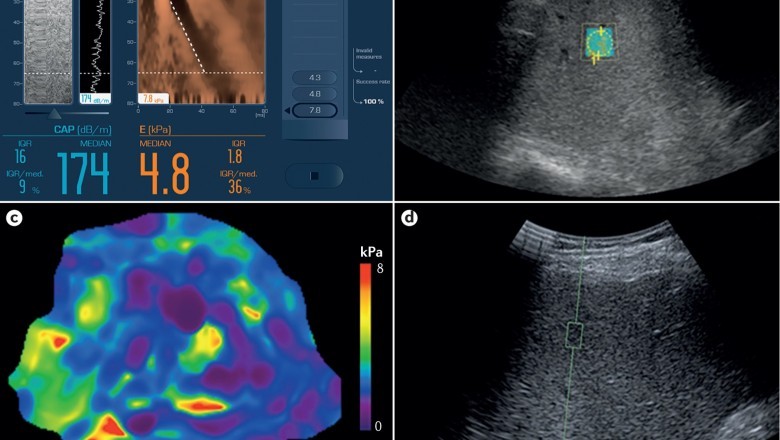

November 2019: SimonMed Imaging is the first to provide advanced screening for fatty liver disease. The VIDA 3T MRI helps to detect fibrosis resulting from fatty liver disease or other chronic liver diseases. It uses MRE (magnetic resonance elastography) that combines sound waves with MRI to develop an elastogram (visual map) to show the stiffness of the body tissue, thus offering radiologists with color contrasted clear visual, maximizing accuracy, and limiting error.